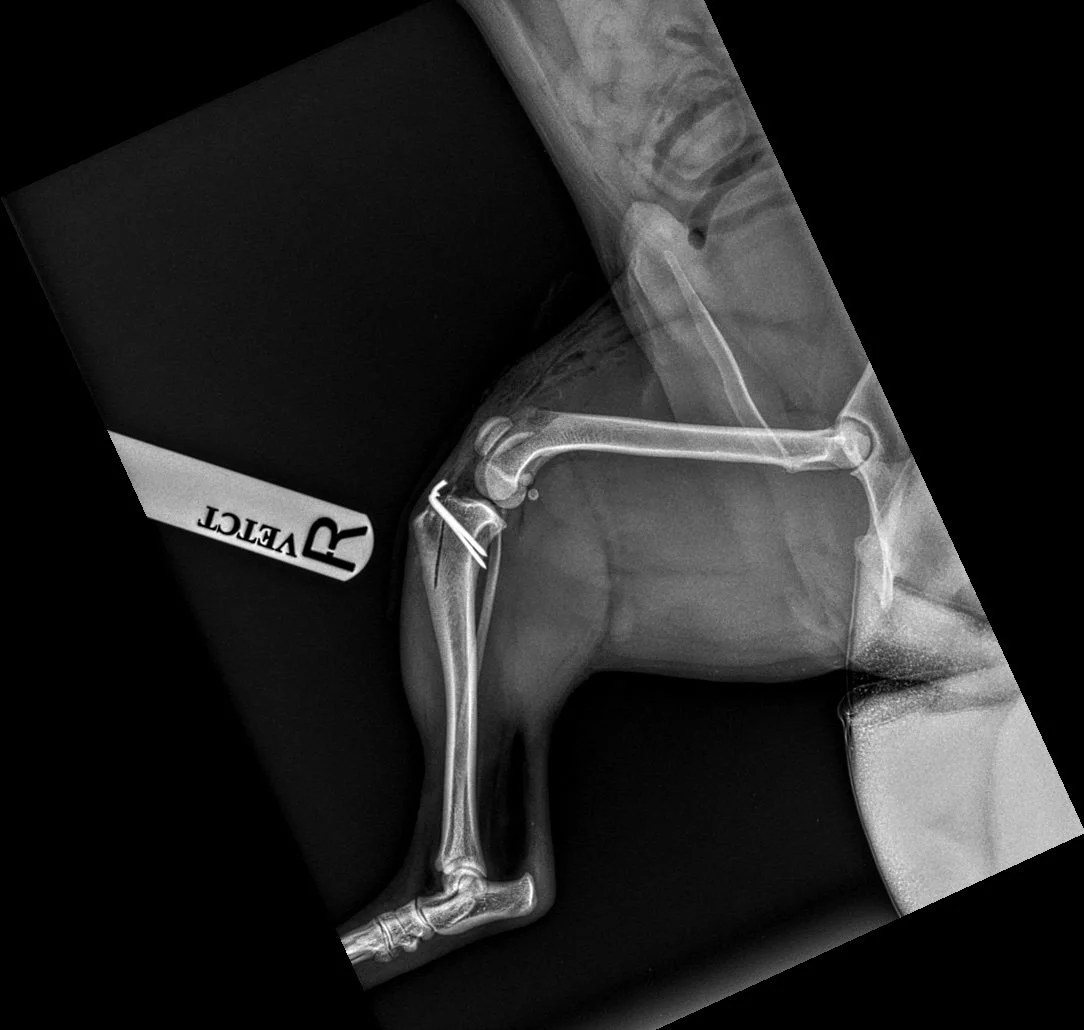

TPLO (Tibial Plateau Levelling Osteotomy)

What is TPLO Surgery?

Tibial Plateau Levelling Osteotomy (TPLO) is a surgical procedure designed to address CCL injuries by altering the biomechanics of the knee joint. Instead of replacing the damaged ligament, TPLO changes the angle of the tibial plateau (the top part of the shinbone) to stabilize the joint during weight-bearing activities.

1. Preoperative Assessment: Detailed radiographs are taken to measure the existing angle of the tibial plateau and plan the surgical approach.

2. Surgical Technique: Under general anaesthesia, a curved cut (osteotomy) is made in the top portion of the tibia. This segment is then rotated to achieve a more level orientation, typically aiming for an angle between 5 to 6 degrees.

3. Stabilization: The repositioned bone is secured using a specially designed metal plate and screws, ensuring stability as the bone heals in its new alignment.